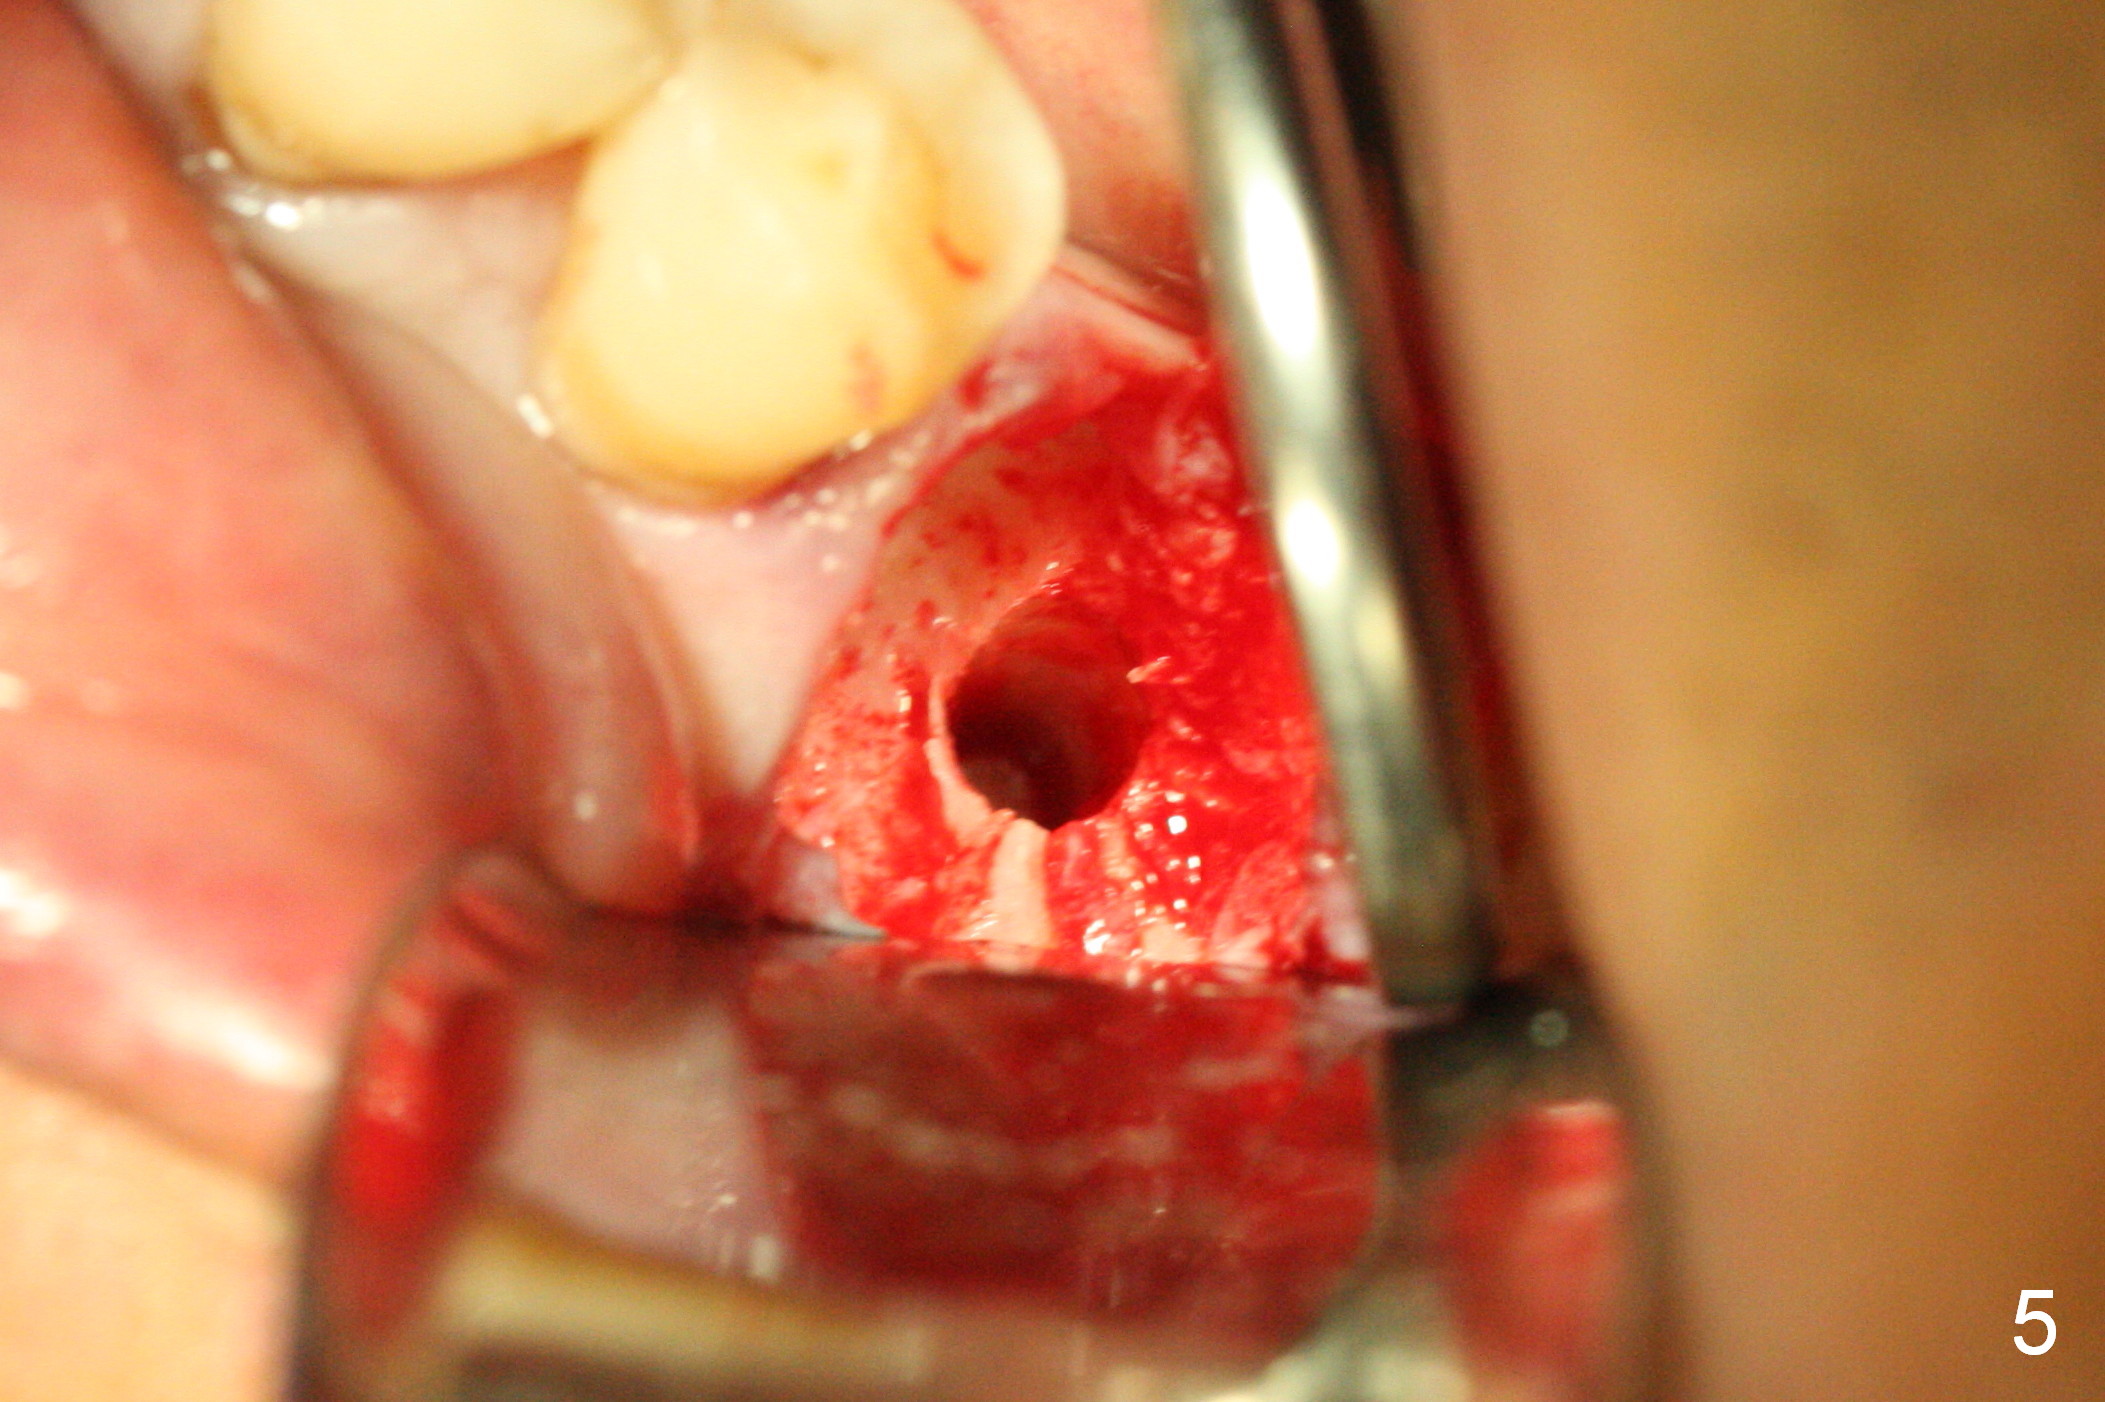

The asymptomatic tooth (#19) has a midbuccal fistula (Fig.1 <). The mesiobuccal pocket is 10 mm with purulent discharge from the sulcus (Fig.2,3). The mesiobuccal wall defect is confirmed when the tooth is extracted. Osteotomy is initiated lingually in the septum following septal crestoplasty (flattening) (Fig.4: using 1.6 mm drill for 9 mm). Since the lingual portion of the osteotomy is higher, it is difficult to use drill with stopper. For the narrow septum osteotomy, multiple drills are used sequentially (Fig.5 after 4.3 mm drill). A 4.5x11 mm dummy implant is placed (Fig.6) apparently too deep. When a 5x11 mm IBS implant is being placed, the depth is tightly controlled (Fig.7). The implant is apical to the lingual crest, whereas there is ~ 2 mm implant exposure buccally. That is, there is a large gap mesiobuccally (Fig.8), which is filled with .5-1.5 mm allograft (Fig.9 *). A 6.5x5.7(3) mm abutment (A) is placed and trimmed for an immediate provisional (Fig.10 P). The lacerated buccal gingiva is sutured as well as application of Perio Glue.